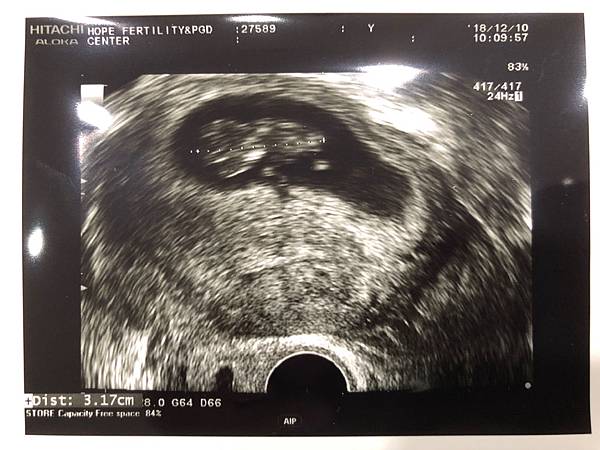

———— 12/10 9W6D 於祈新畢業了 ————

很幸運的打了點滴後出國的這一週我非常有精神,幾乎忘記孕吐這件事。回國後回診,第一次從陳醫師口中聽到「恭喜」,我也這樣默默的畢業了,接下來就是要決定產檢的地點和是否要選擇羊膜穿刺還是NIPT。剩下的3個胚胎我們決定留著,繼續付了1年的保管費用。希望日後的孕期也順順利利。